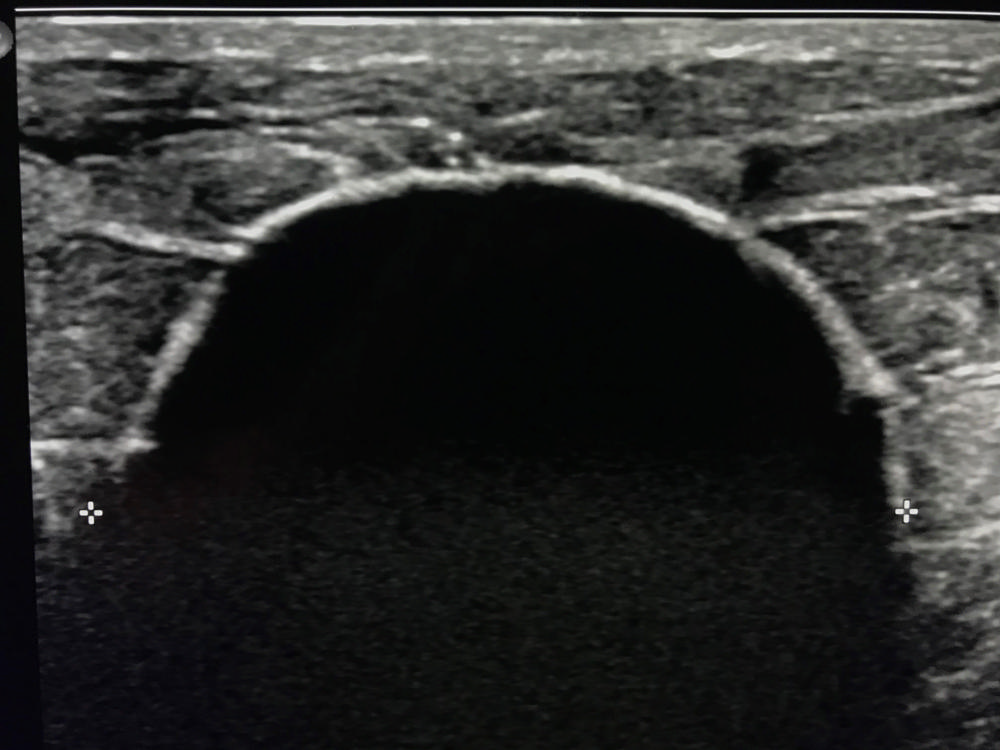

Figure 10. Ultrasound following cryoablation demonstrates very visible black "ice ball" (+) completely engulfing breast cancer which is no longer seen.

High-res (TIF) version